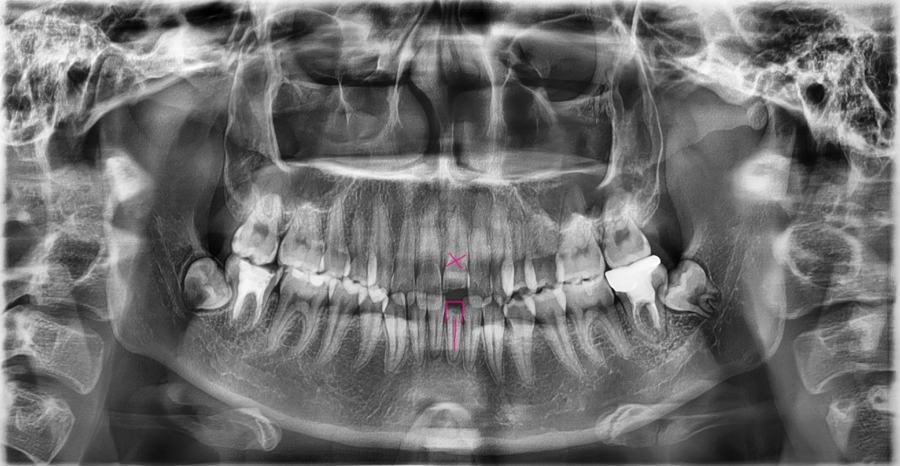

교통사고 이후 앞니가 절반가량 깨진 상태로

내원하신 환자분의 엑스레이입니다.

겉으로 보기에는 파절 부위만 문제로 보일 수 있지만,

치아 뿌리와 주변 잇몸뼈까지 함께 확인이 필요했던 사례입니다.